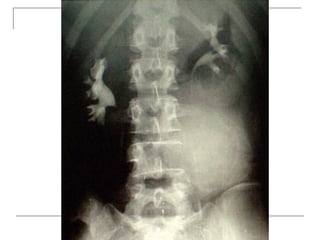

Plain radiograph

   AP

-loss of lumbar lordosis

-reduced disc space

-osteophytes

-deformity

-fracture (increase interpedicular distance)

-osteoporosis

-pedicle disruption

   Lateral

-fracture/wedging

-kyphosis

-spondylolisthesis

   Oblique

-spondylolysis (SCOTTIE DOG)

Plain x-rays

Plain radiograph  AP -loss of lumbar lordosis -reduced disc space -osteophytes -deformity -fracture (increase interpedicular distance) -osteoporosis -pedicle disruption

Lateral -fracture/wedging -kyphosis -spondylolisthesis  Oblique -spondylolysis (SCOTTIE DOG)